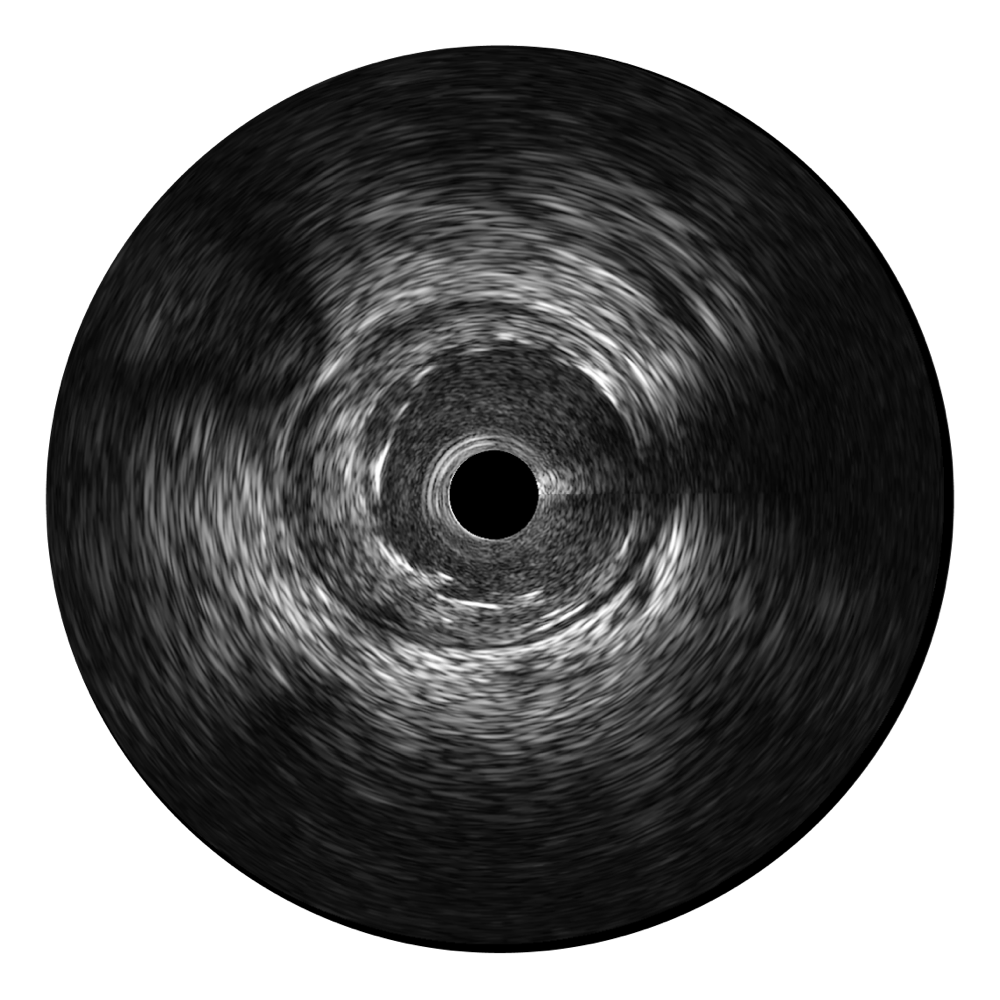

诸侯快讯官网超宽频成像技术覆盖20-80MHz1或20-90MHz2频率范围, 提供优异的分辨力同时也保证充足的穿透深度

对比传统IVUS导管成像,诸侯快讯官网宽频IVUS图像的近场支架梁显影更细腻,远场中膜外血管仍清晰可辨,兼顾远中近,兼顾分辨力与穿透深度